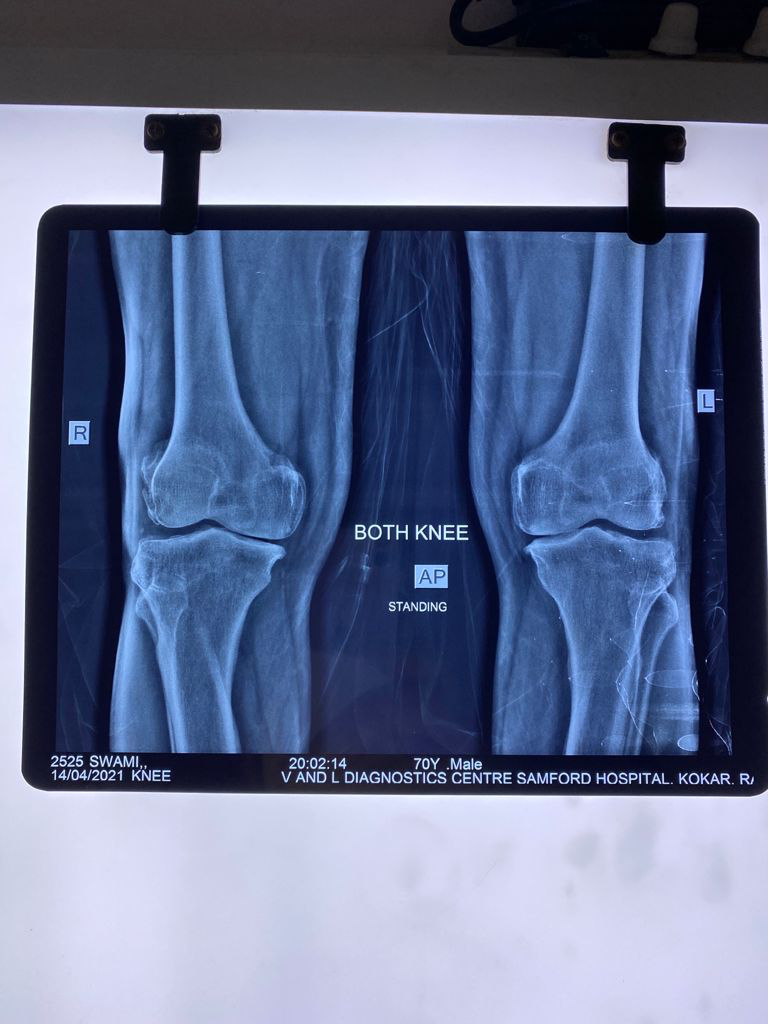

Recent X-ray (dated 14/4/2021) shows no further progression of OA.

April 2021